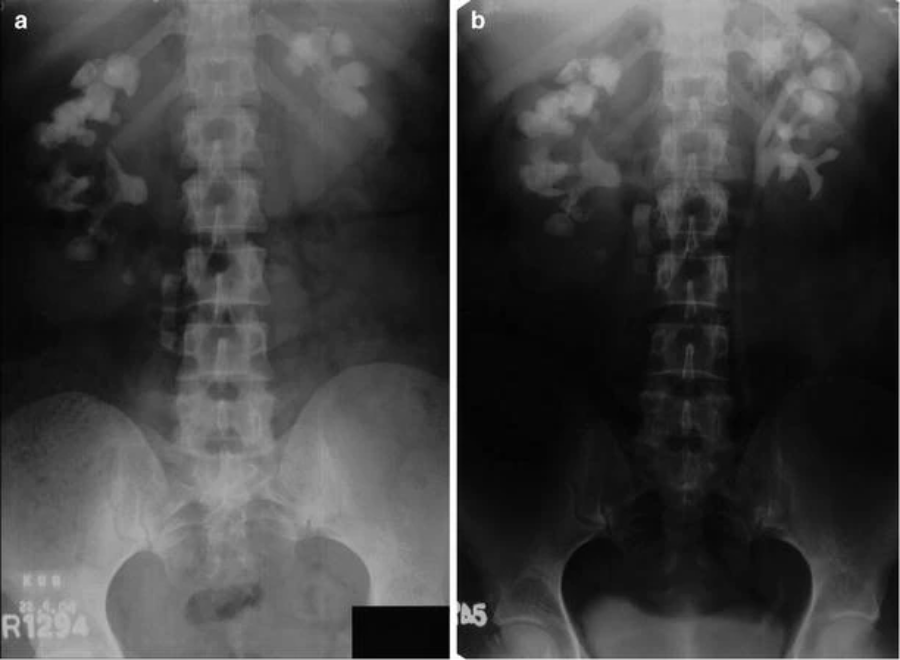

右经皮肾镜取石术 (PCNL) 中所有潜在束的预扩张导丝放置,用于鹿角。( a ) 普通 KUB 显示双侧鹿角形结石。( b ) 静脉尿路造影 (IVU) 胶片。( c ) 右侧 PCNL 的初始导丝放置。( d ) 第二次导丝放置。( e ) 第三次导丝放置。( f ) 第四次导丝放置

尽管有所有这些技巧可以通过单个肾造口术改善取石效果,但重要的是要记住,如果在无法触及的花萼中有大量结石,第二次肾造口术仍然是最快和最有效的取石方法清除。在预期使用两个或更多束的情况下,我们建议在扩张任何束之前,在计划进入的每个盏上进行初始穿刺和导丝放置(图41.7a-f)。通过在每次穿刺的透视引导下使用造影剂,显着有助于多道 PCNL。由于 Amplatz 鞘的渗漏和与管道相关的外渗,在管道扩张后,造影剂的使用变得困难。对于随后不需要的任何预先计划的管道,只需在程序结束时移除导丝。